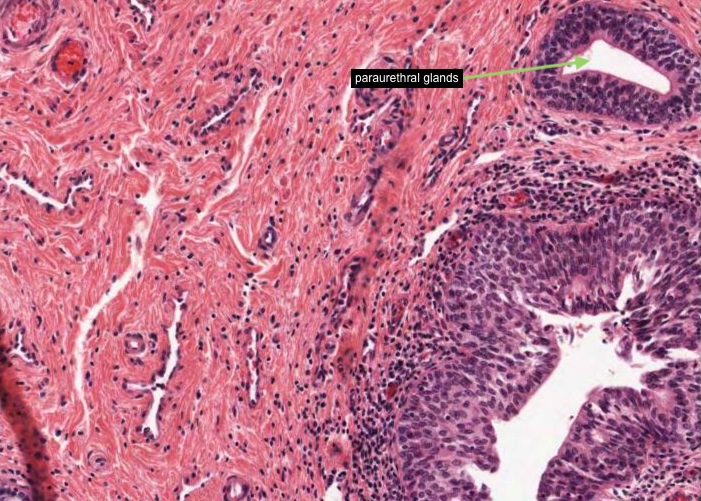

Locate the urethra lumen. The three layers of the ureter are repeated, but they are thicker and the muscle layers are not as distinct as you will see when you view this section. I think the muscle in this part of the female urethra is smooth muscle. I can't see any skeletal muscle which would indicate this was the middle part of the female urethra.

The mucosa has longitudinal folds which you may now appreciate better if you relook at the low magnification image in the previous item. The epithelium of the urethra will vary according to the region from which a section is taken. In this image, taken near the bladder, it is urinary/transitional epithelium (urothelium), at the external opening it is stratified squamous epithelium, and between those two ends the epithelium is pseudostratified or stratified columnar.

Small outpocketings of mucus-secreting cells form clusters in the epithelium and extend into the lamina propria as simple paraurethral glands. Those located within the epithelial layer are examples of intra-epithelial glands.